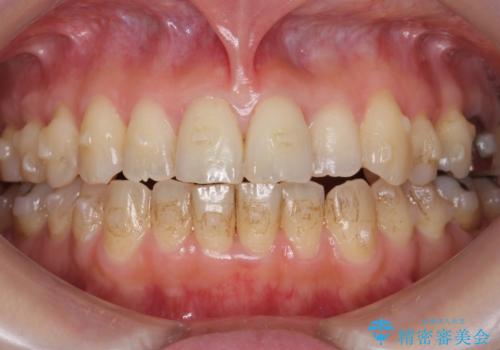

前歯のガタガタ 治療期間がかかっても良いので非抜歯でマウスピースで

- 前歯のガタガタを主訴に来院。

前歯は開咬傾向であり、小臼歯から大臼歯にかけてもオーバージェットは非常に小さく咬耗していました。

非抜歯で前歯の重なりを作るのは難しいとご説明しましたが、インビザラインでできるところまで並べていくことになりました。

結果、非常に真面目に治療に取り組んでいただき、期間はかかりましたが予想以上の結果を得ることができました。